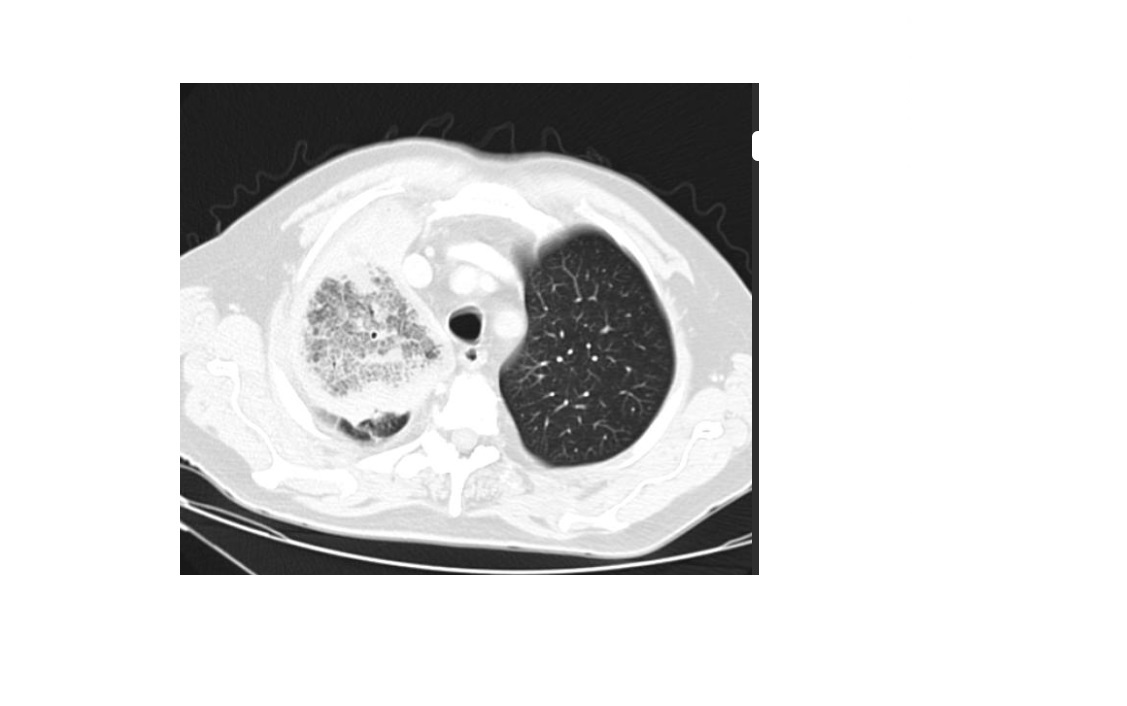

Bilateral Renal oncocytomas

+ **chromophobe RCC